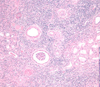

Acute allograft rejection; form of acute interstitial nephritis; where lymphyocytes actually infiltrate the tubules

Acute pyelonephritis; neutrophil infiltration

Bacteria in Acute Pyelonephritis; look like pale blue smudges

Fungus (arrow) in Acute Pyelonephritis

WBC casts in the medulla in acute pyelonephritis